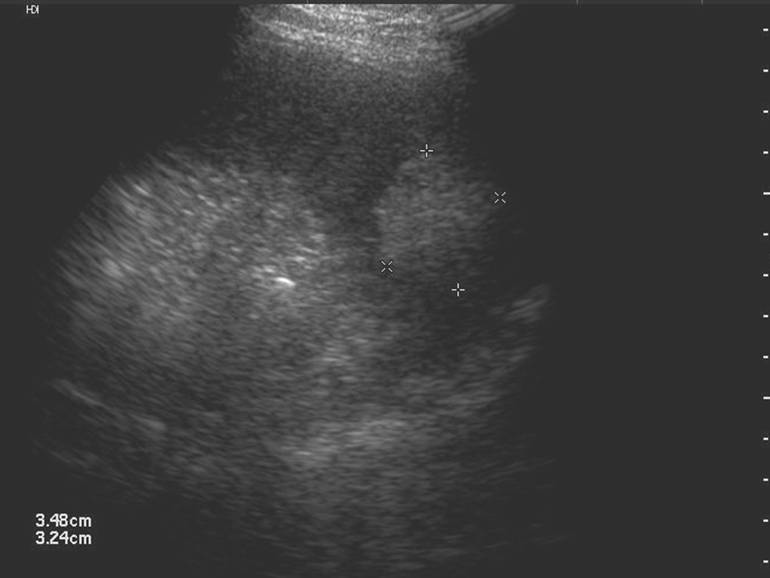

中央型破裂(脾挫伤)

破裂发生在脾实质内,引起实质挫伤出血。

声像表现:实质内片状或团块状回声增强,或强弱不均,发展为局限性低或无回声区,也可发展成多发片状低回声区。